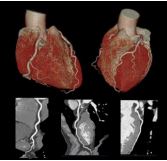

2. 「Precise Cardiac (プレサイス・カーディアック)」 AIを活用した心臓専用のモーションフリー画像再構成機能である。 新たに搭載されたAIベースの高度な補正技術により、心臓の拍動によ るブレを補正、画質を大幅に向上させる。ヘリカル撮影とコンベン ショナル撮影どちらにも対応し、あらゆるシチュエーションにおいて 診断精度の向上に貢献していく。